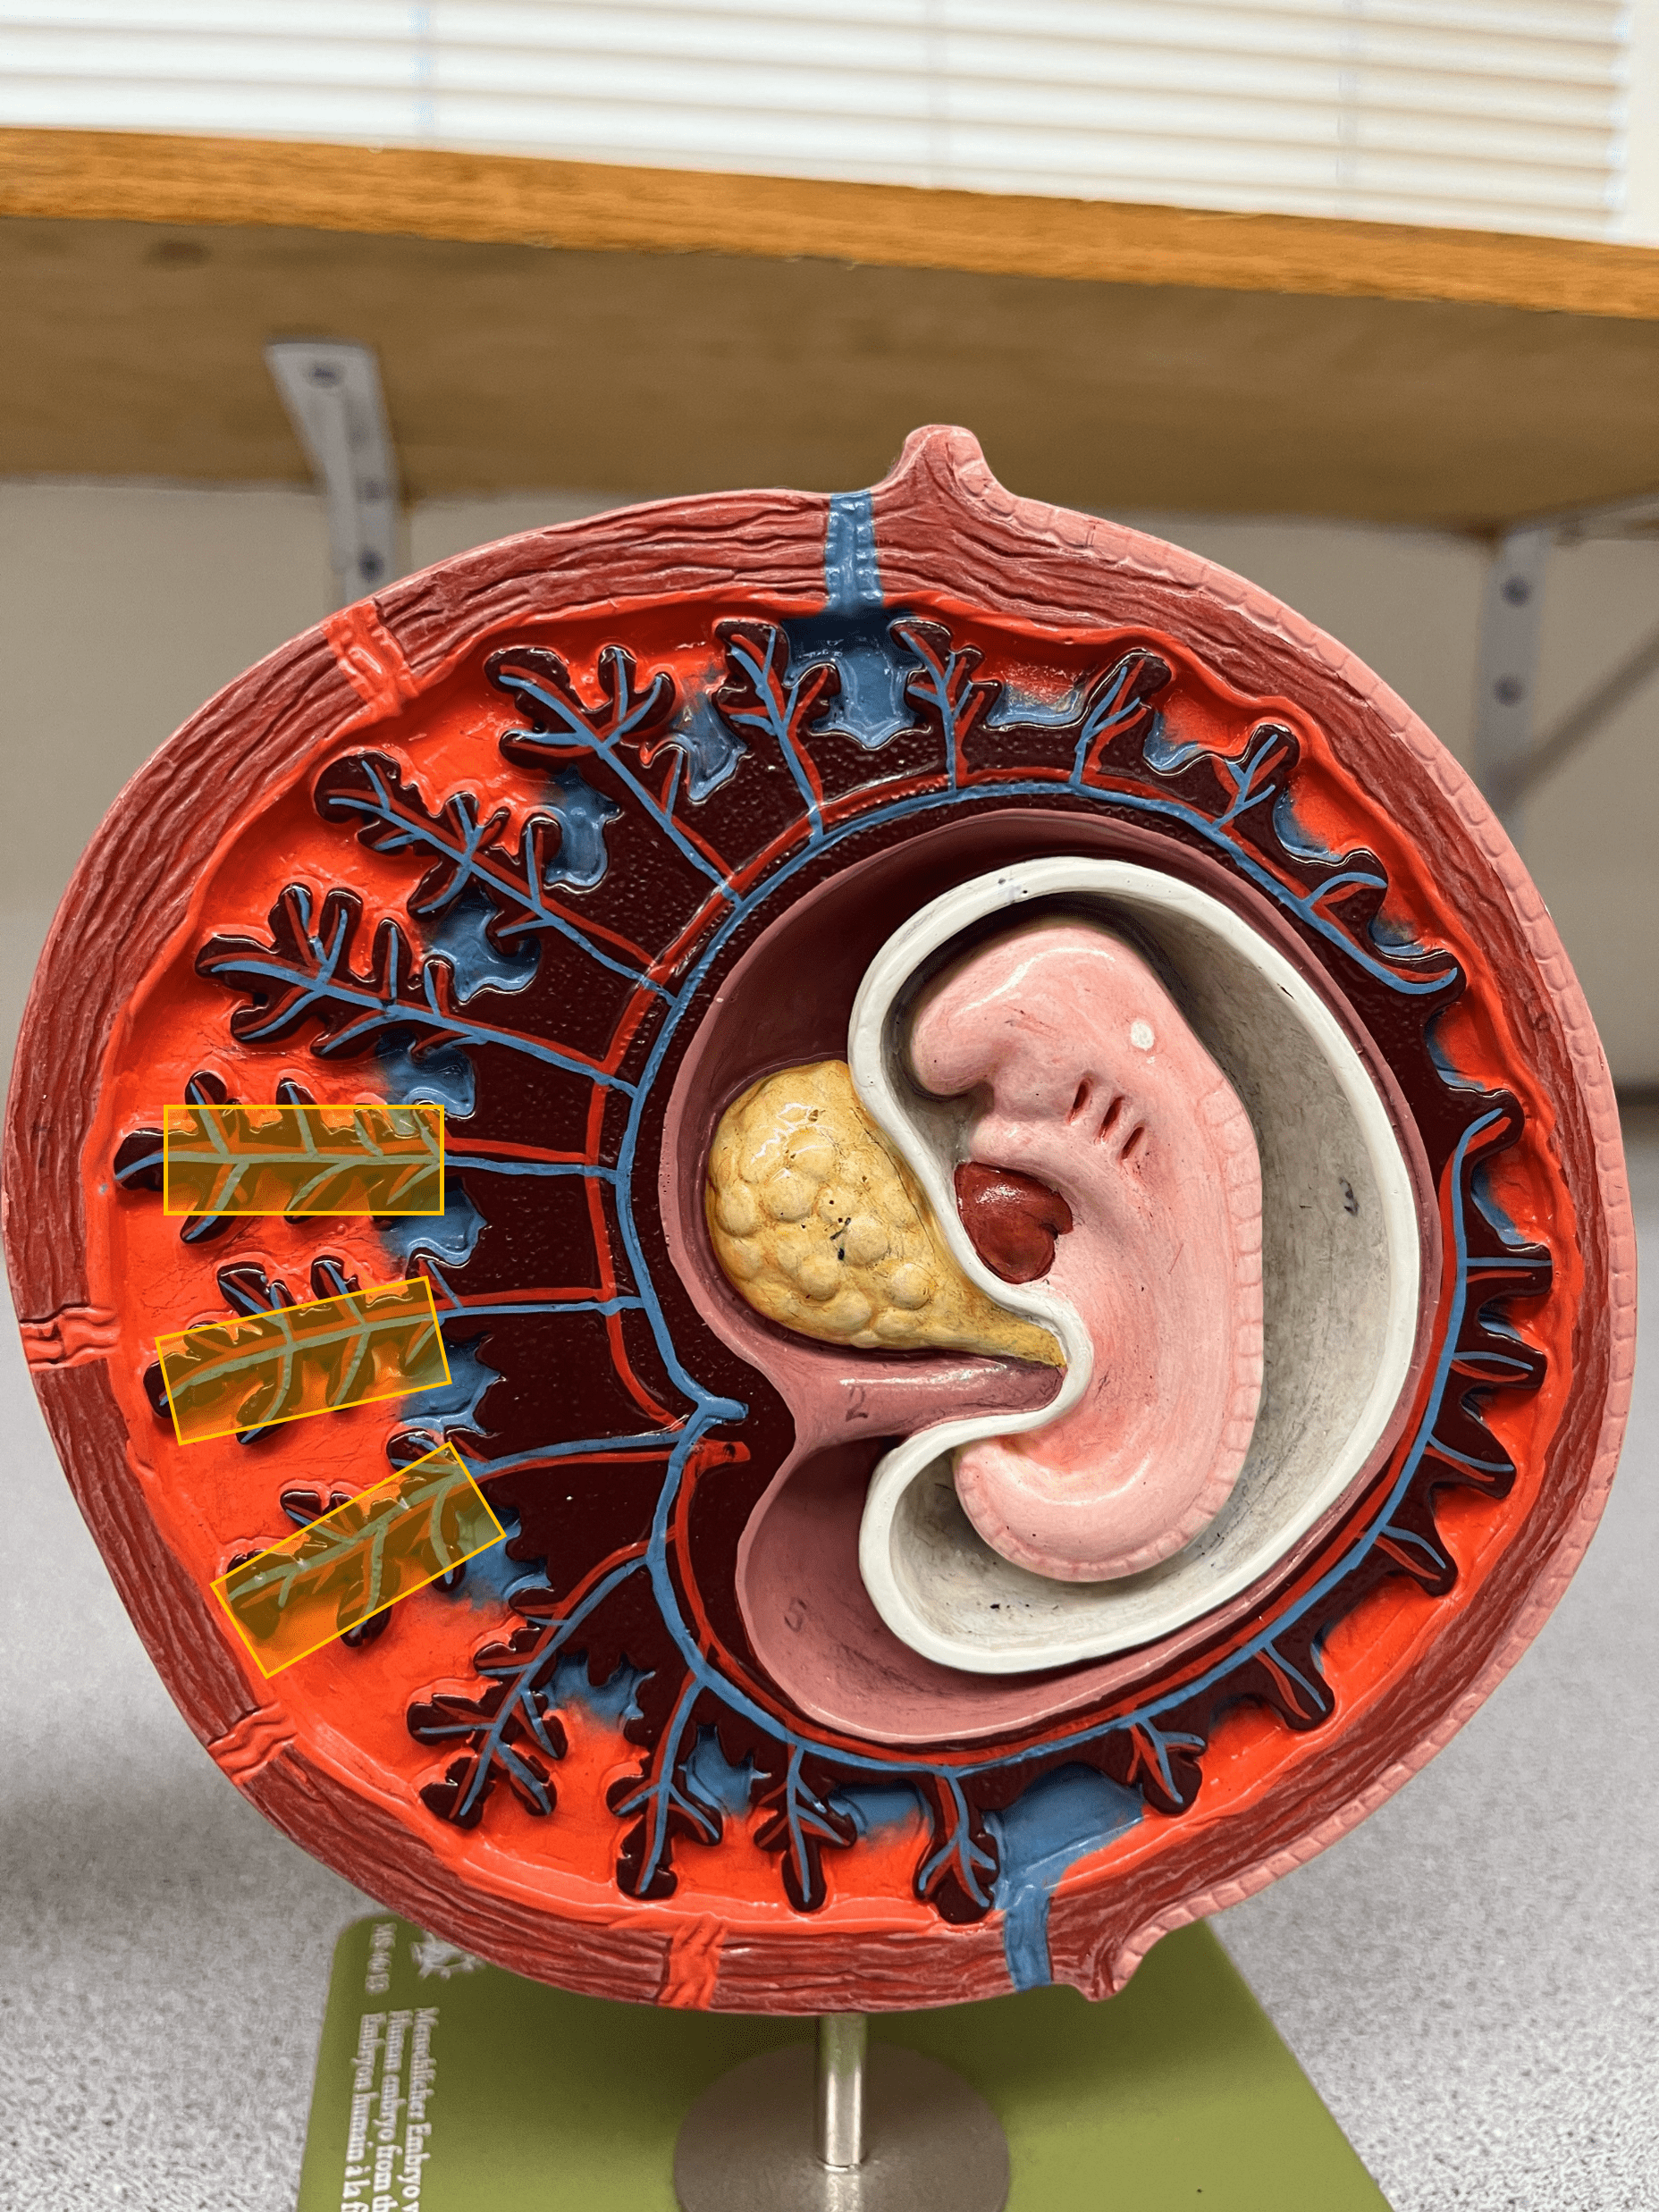

• Model of the 30-day embryo.

• Extensions of the chorion that bring fetal and maternal blood into close proximity to allow diffusion of nutrients and wastes.

• Contains vessels.

• Model of the 30-day embryo.

• The maternal portion of the placenta that exchanges nutrients and wastes with chorionic villi vessels.

• Also known as a placental sinus.